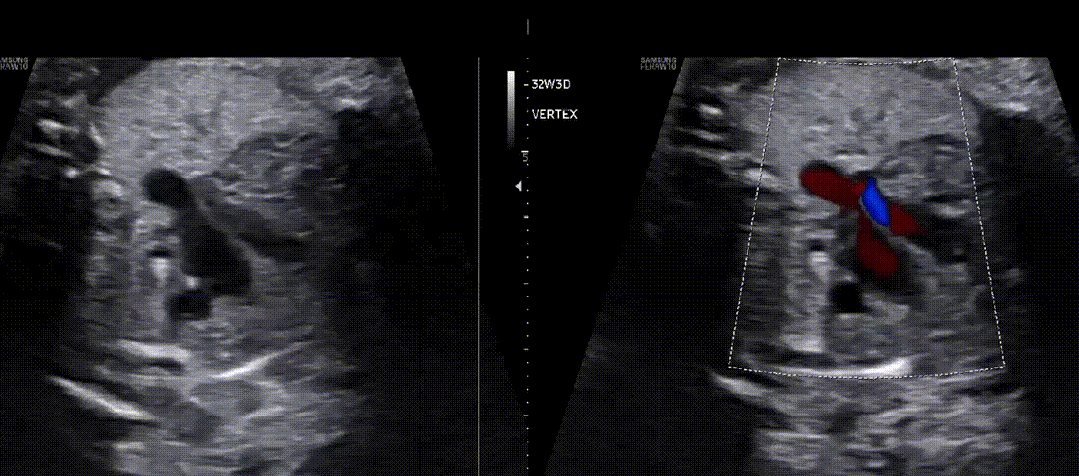

图28半月瓣狭窄同侧弓的逆流。(上图)严重右心室流出道梗阻,其中3VT看起来有些正常,但彩色多普勒显示动脉导管逆行(蓝色)。(下图)主动脉弓的矢状在2D图像上看起来正常,但彩色多普勒成像显示导管弓的逆(蓝色)流。

另请参阅视频17  :

右心室流出道狭窄,其中 3VT 显示正常,但彩色多普勒显示动脉导管内有逆流(蓝色)。